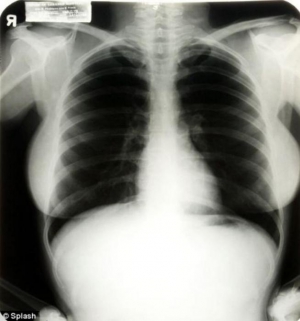

В конце июня в казино "Планета Голливуд" пройдет аукцион, на котором будут выставлены личные вещи кинодивы Мэрилин Монро. В числе лотов — мебель актрисы, духи, но особую ценность, по мнению организаторов мероприятия, представляют рентгеновские снимки грудной клетки звезды.

Снимок был сделан в ноябре 1954 года в Ливанской больнице Кедры (Флорида, США). Актриса делала этот снимок для подготовки операции по поводу эндометриоза, который причинял ей постоянный дискомфорт. Также есть видеоматериал, на котором запечатлен выход Монро из больницы через два дня после рентгена. Следует отметить, что в тот момент дива выглядела не столь эффектно, как обычно.

На рентгеновском снимке стоит имя Мэрилин Ди Маджио. Тогда актриса еще была замужем за знаменитым баскетболистом. Как уточняют организаторы аукциона, снимок был сделан несколько месяцев спустя после окончания съемок фильма "Зуд седьмого года".

Молодой врач, который тогда работал в рентгеновском кабинете больницы, взял снимок для преподавания в медицинской школе и демонстрации студентам. Позже снимок перешел его дочери, которая выставила его на продажу. Организаторы аукциона оценивают снимок в 800-1200 долларов.

По мнению представителя Julien"s Auctions, "к снимку должно быть проявлено особое внимание, поскольку это необычный взгляд на легенду".